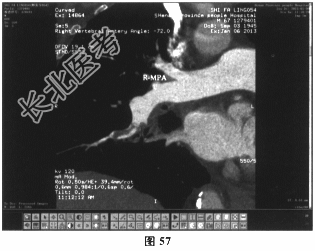

- 多项选择题5.[提示]患者肺动脉CTA(图57~图60):右肺中动脉及右下肺动脉低密度充盈缺损。下肢静脉多普勒超声未见异常。综合上述检查结果, 明确诊断为

A、肺栓塞